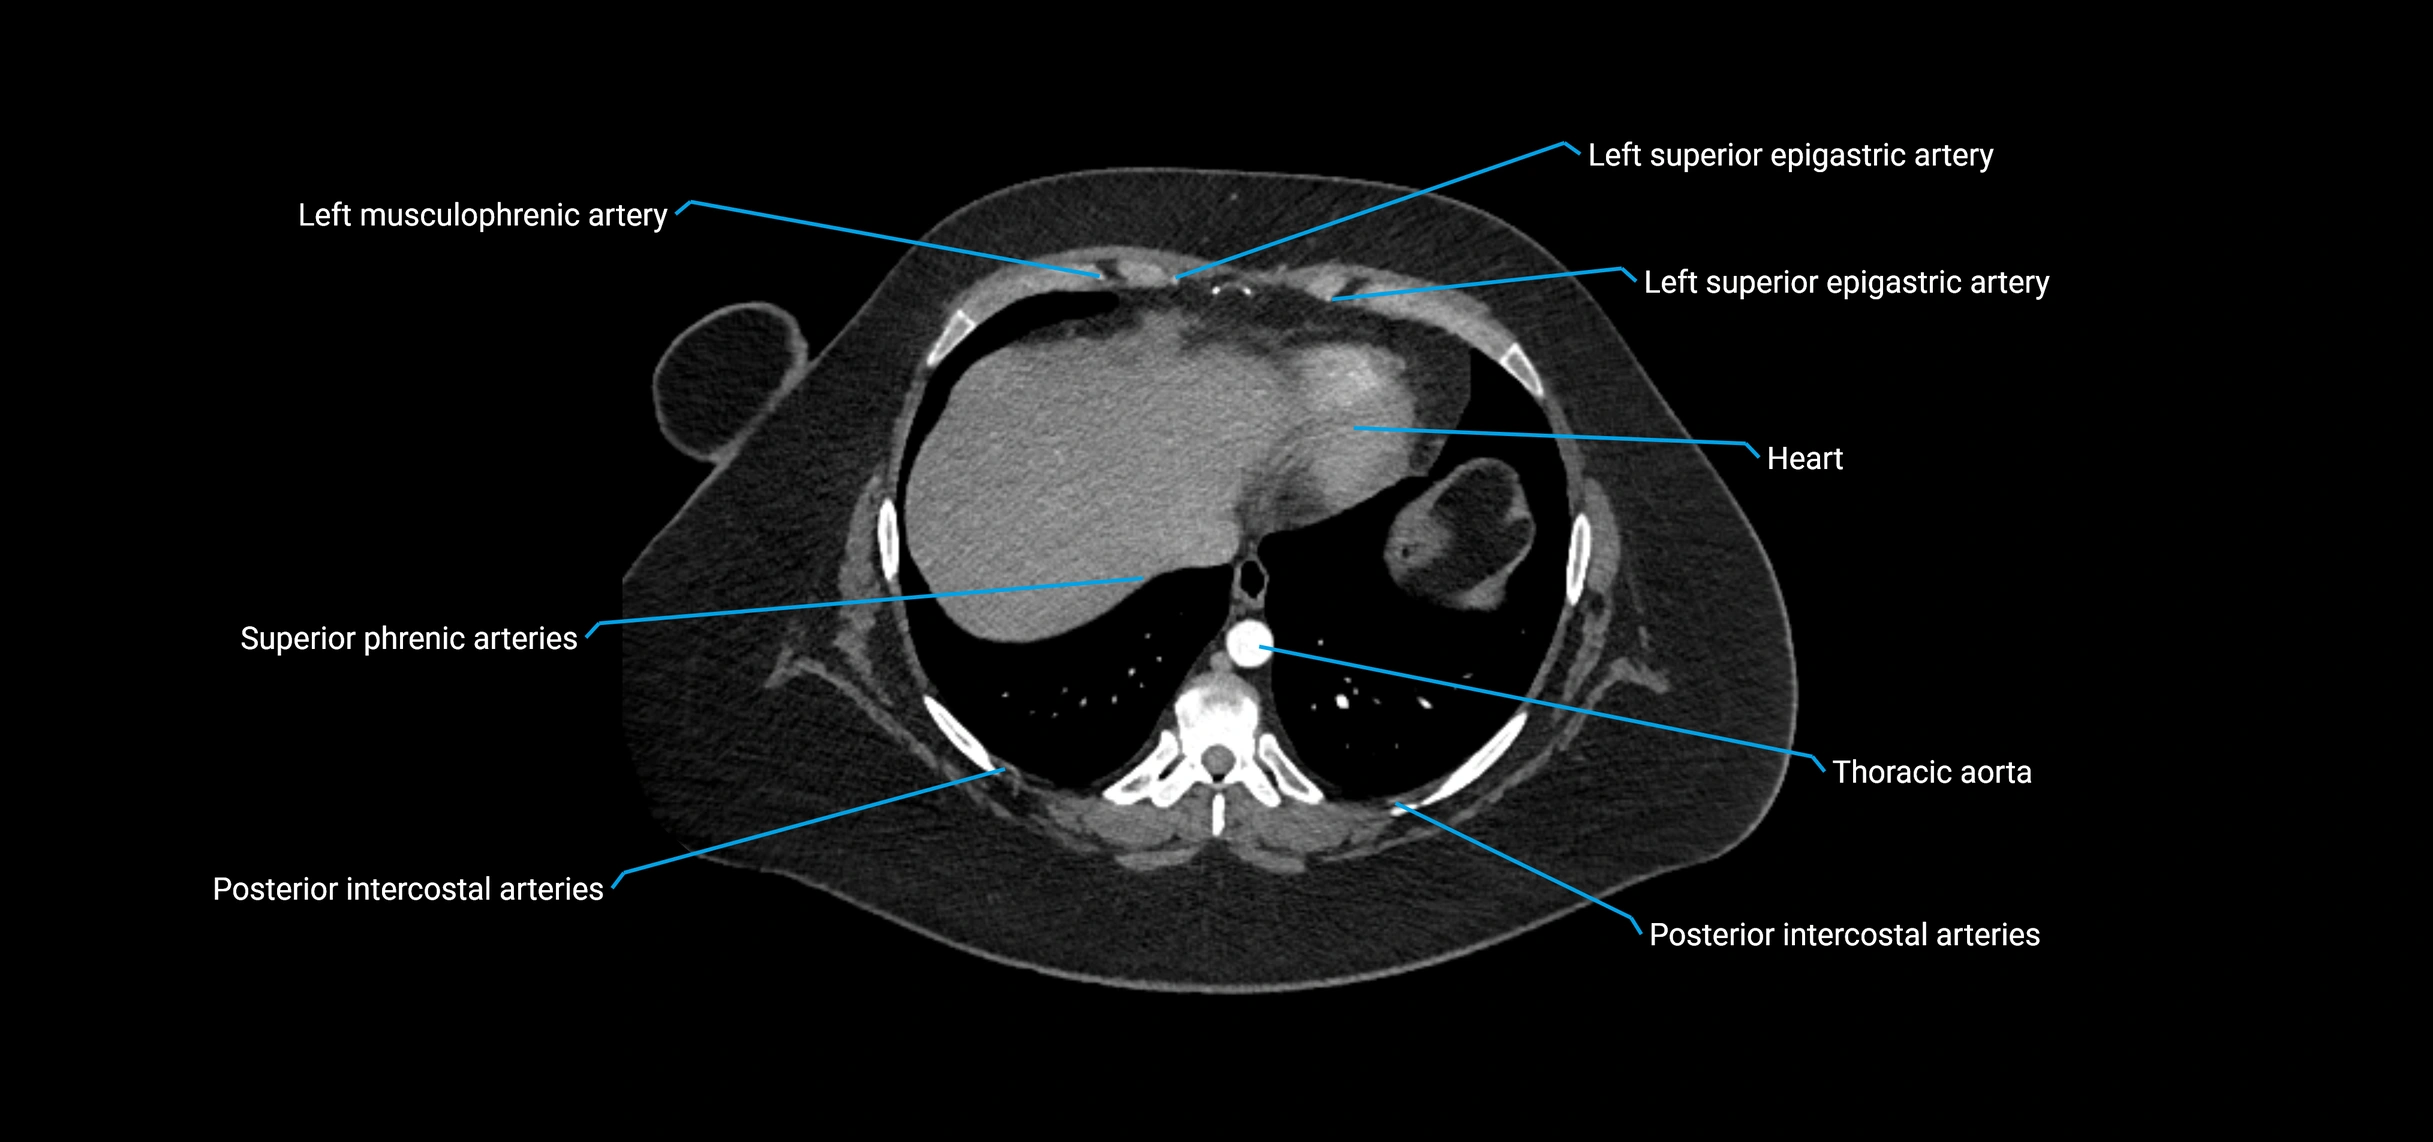

CT Appearance

Non-contrast CT:

• Appears as a tubular soft tissue structure anterior to vertebral bodies

• Calcified atherosclerotic plaques appear as hyperdense foci along the wall

• Useful for screening abdominal aortic aneurysm (AAA) size and mural calcification

Contrast-enhanced CT (CTA):

• Gold standard for abdominal aortic imaging

• Provides excellent detail of lumen, wall, aneurysm, thrombus, and branch vessels

• Multiplanar and 3D reconstructions help in aneurysm measurement, stent graft planning, and dissection evaluation

• Detects acute rupture, traumatic injury, or occlusion with high sensitivity